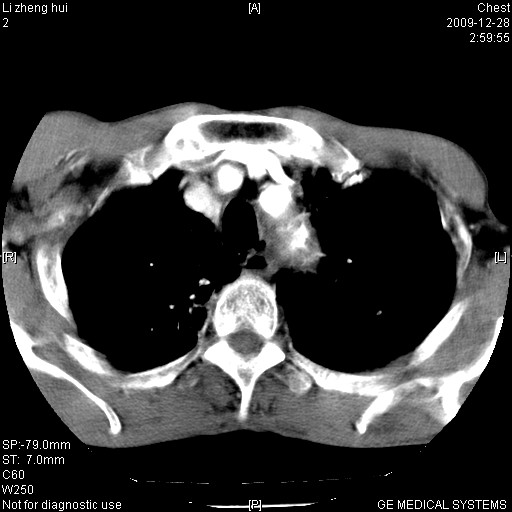

标题: CT23859:胸主动脉瘤

男  79岁 胸部痛急诊入院,晚上做的增强

考虑主动脉瘤?(增粗、钙化、壁血栓?)

支持降主动脉夹层

支持降主动脉瘤,不考虑夹层

动脉瘤伴附壁血栓

1)考虑胸主动脉壁间血肿或夹层动脉瘤。2)多发性肝囊肿。

1)考虑胸主动脉附壁血栓或夹层动脉瘤。2)多发性肝囊肿。